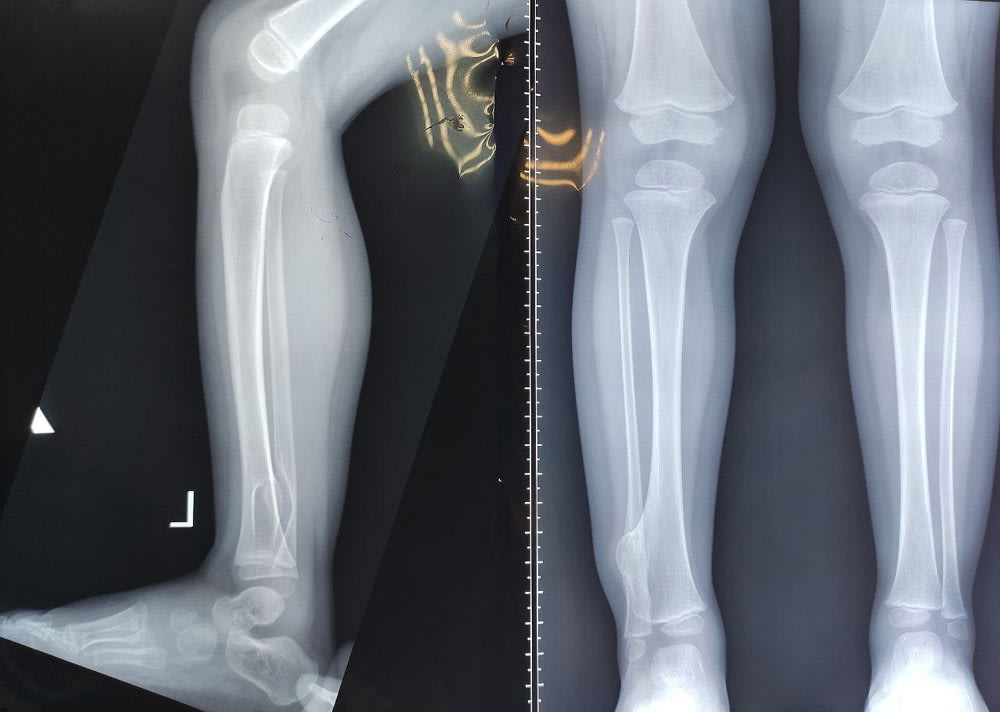

– Ребенок, 2,5 года, поступил к нам с диагнозом «экзостозная болезнь. Костно-хрящевые наросты на костях удаляются только по показаниям. В данном случае экзостоз начал деформировать голеностопный сустав, давить на нерв, доставлять ребенку дискомфорт при ходьбе, поэтому было принято решение об оперативном вмешательстве. Во время операции выделен нерв, произведено удаление экзостоза в пределах здоровых тканей, – сообщил врач травматолог-ортопед Глеб Большаков.

Как рассказала мама ребенка, шишку на левой ноге обнаружили случайно: дочь каталась на самокате, упала, на всякий случай решили прощупать все кости и обнаружили уплотнение. Поскольку ребёнок встал и пошёл дальше, родители не стали экстренно обращаться к врачу, а записались на прием к ортопеду. Сделали снимок, на котором врач увидел большую шишку. Маленького пациента направили в отделение травматологии и ортопедии Ивано-Матренинской больницы, сделали операцию.